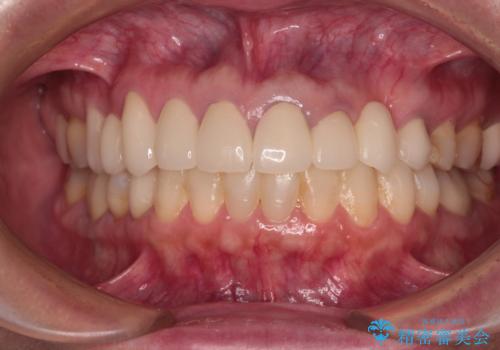

欠損部や、銀歯やむし歯の大きな歯はセラミッククラウンやブリッジに、小さいむし歯はセラミックインレーにて治療を行うこととしました。

歯肉の状態がとても、短期間でスムーズに治療を終えることができました。